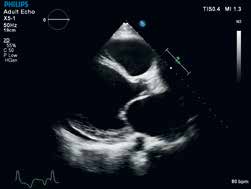

X5-1纯净波矩阵探头对二维、三维实时图像清晰度的体现。

纯净波矩阵探头还包括支持儿童三维成像的X7-2和支持3DTEE应用的X7-2t